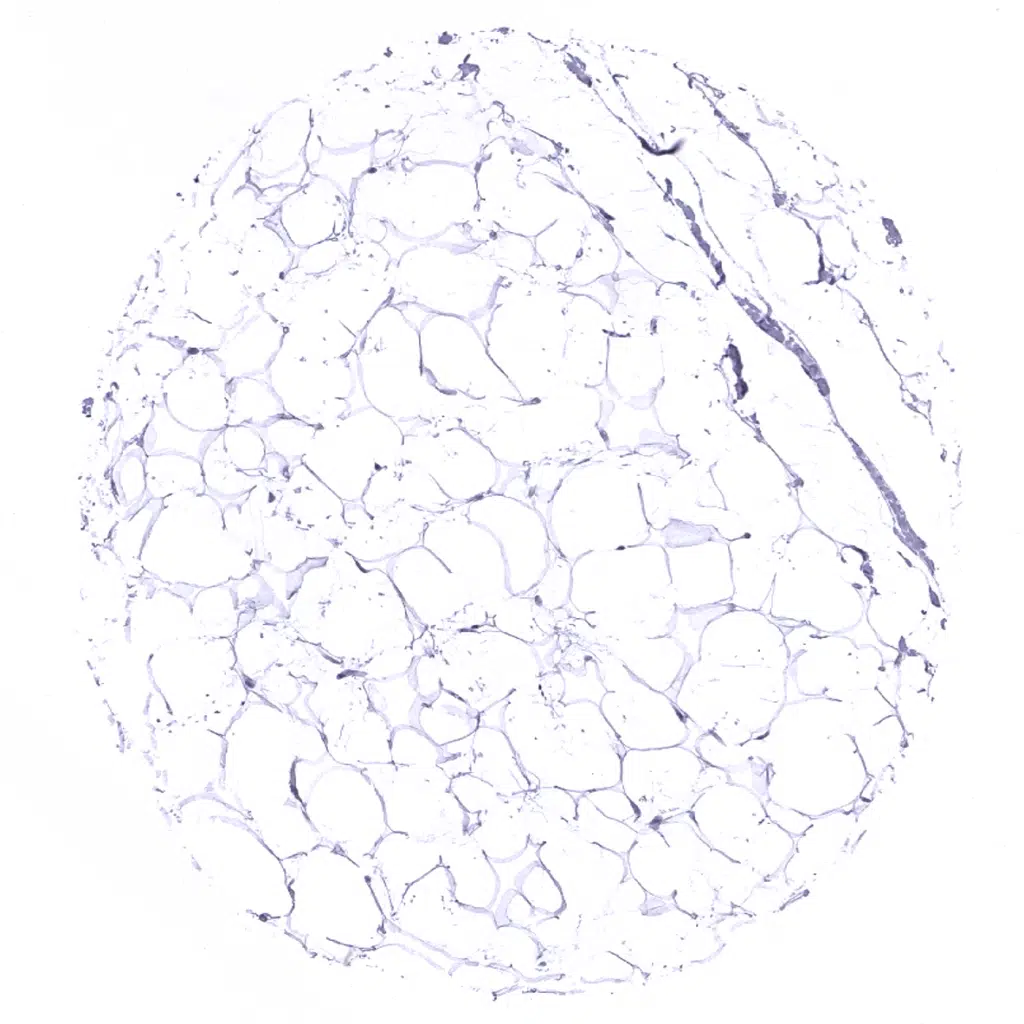

Fat